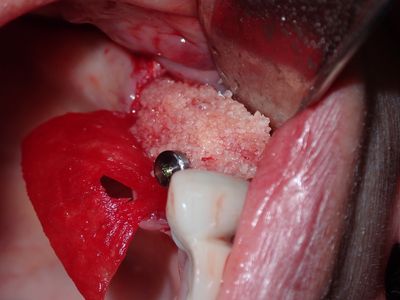

Mtiu - implant with bone expansion and graft

13 root is angled apex to the distal, 14 osteotomy positioned in region of thin bone, prepared to just under 2mm, remainder with densah drills, implant placed with bone around it countersunk. buccal region grated with sticky bone from 50/50 Mineralized cortical/cancellous followed by collagen membrane soaked in prf fluid, additional fibrin membrane overtop.